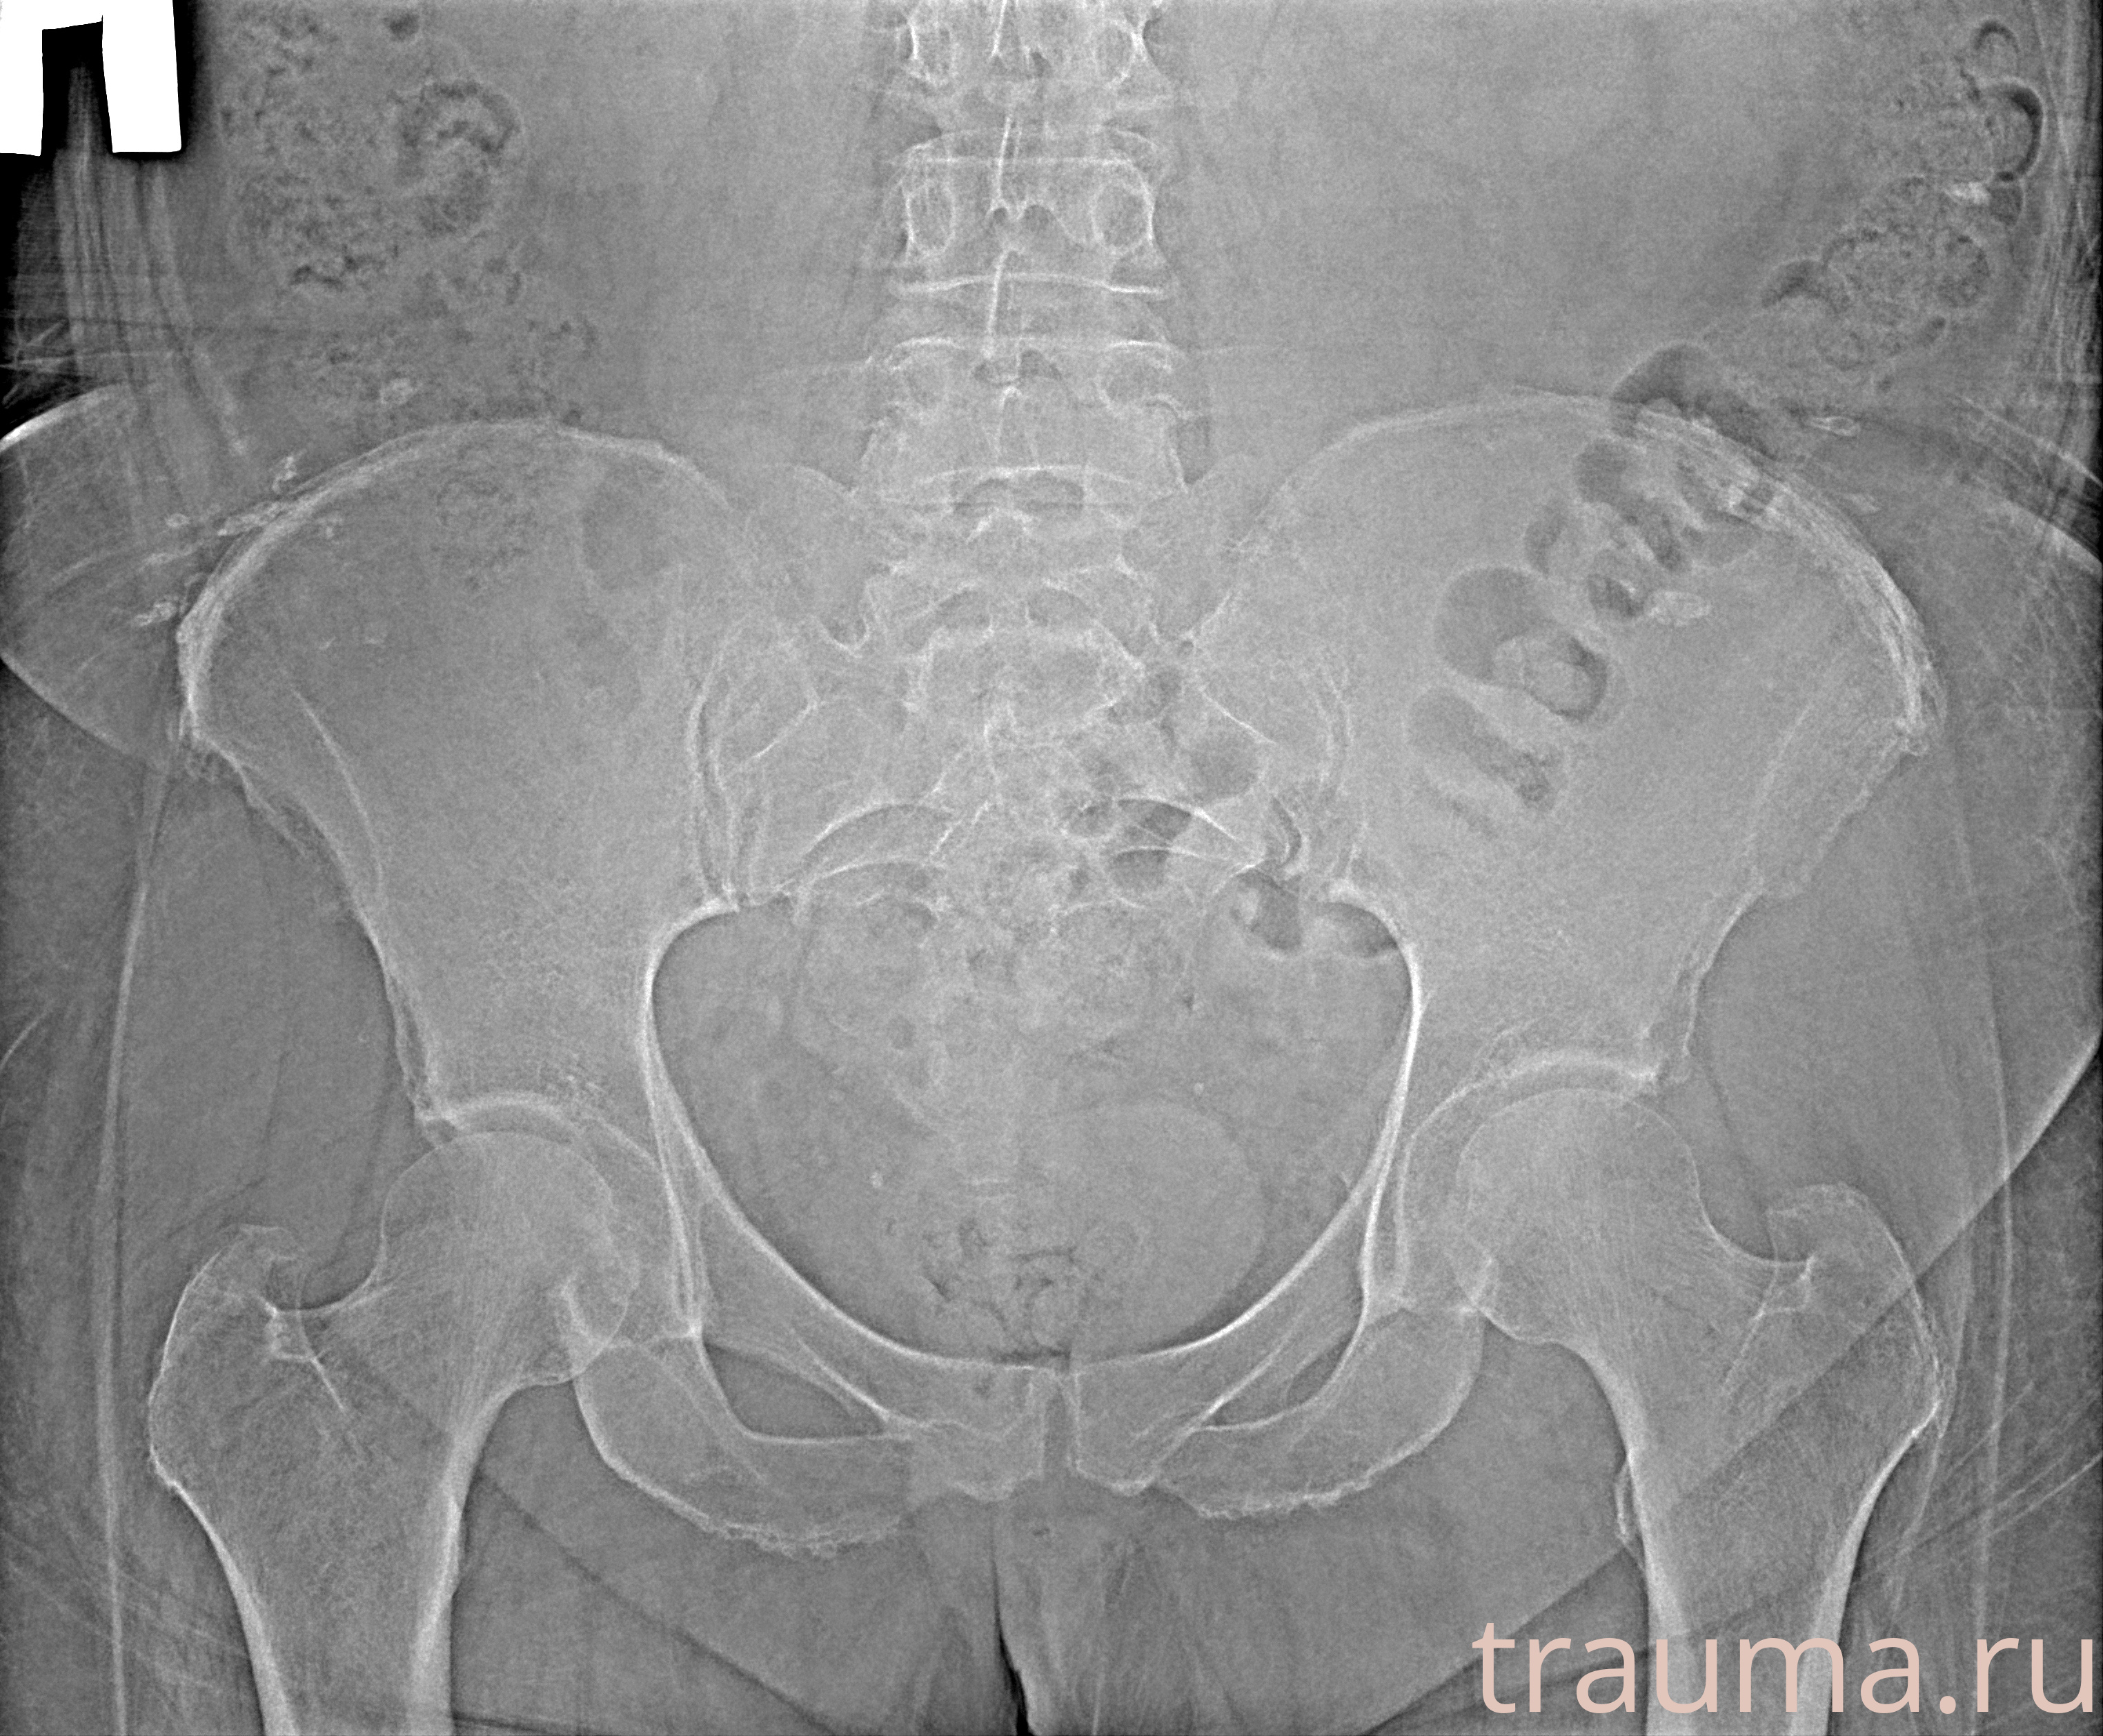

Рентген на дому: по вашему адресу приезжает врач-рентгенолог, травматолог-ортопед с мобильным рентгеновским аппаратом, проводит диагностику травмы или заболевания, делает необходимые рентгенограммы, дает рекомендации по дальнейшему лечению. Получить качественные снимки в домашних условиях возможно благодаря уникальной методике, разработанной МосРентген Центром для института  Склифосовского